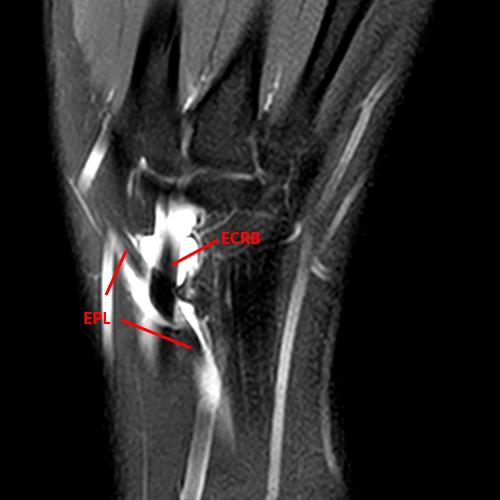

Distal Intersection Syndrome occurs where the EPL crosses dorsal to the extensor carpi radialis longus (ECRL) and extensor carpi radialis brevis (ECRB) tendons (Figure 10). Proposed mechanisms include stenosis from the overlying extensor retinaculum and intrinsic stenosing tenosynovitis. Communication is typically present between these tendon sheaths, and tenosynovitis may secondarily spread from one compartment to the other. These patients present with radial-sided dorsal wrist pain. The fluid-sensitive MRI series demonstrate the involved tendons, which may show thickening of the tendon sheaths, tenosynovitis, edema, and abnormal intrasubstance tendon signal (Figure 12).22,40,41

Figure 12: 21-year-old female with dorsal radial pain and swelling with clinical concern of de Quervain’s tenosynovitis. A fat-suppressed proton density-weighted coronal (12A) and axial (12B) images demonstrate tenosynovitis involving the tendon sheaths of the extensor carpi radialis brevis (ECRB) and extensor carpi radialis longus (ECRL) tendons and the crossing extensor pollicis longus (EPL) compatible with a distal intersection syndrome.